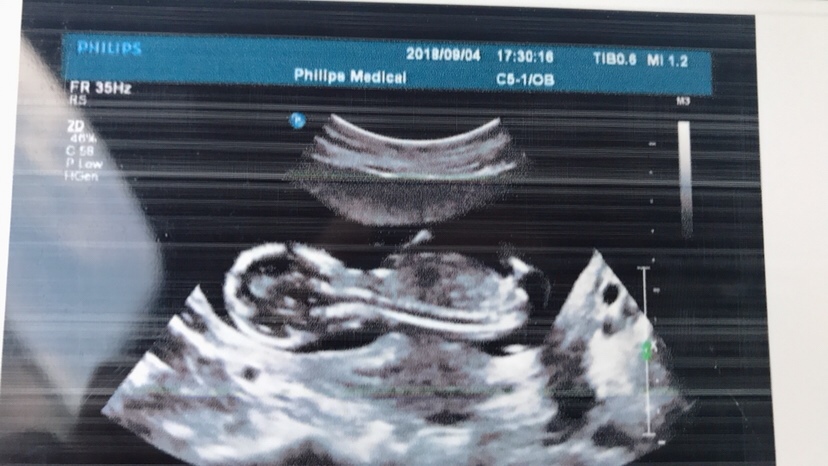

孕22周+0天

大姐你这个怎么看

喜感??:她脑袋瓦特了😂